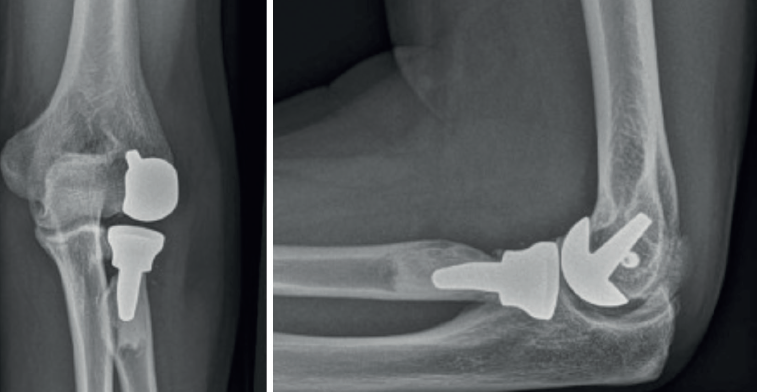

Una alternativa terapéutica prometedora en los casos de cambios degenerativos avanzados del capitellum sin afectación de la articulación ulnohumeral es la colocación de una artroplastia radiocapitelar o Uni-Elbow®(Figura 5).

Inicialmente diseñada para tratar patología degenerativa primaria o postraumática del compartimento lateral del codo, puede ser una opción en casos de fracaso de prótesis de la cabeza radial, inestabilidad residual y daño grave del capitellum. La literatura publicada al respecto es escasa(24,25,26), con pocos casos y seguimientos cortos, pero los resultados son alentadores, puesto que permite restaurar la cinemática del codo al evitar la deformidad progresiva en valgo y el acortamiento del radio. Si bien los resultados clínicos son satisfactorios, la progresión de los cambios degenerativos en la articulación ulnohumeral son frecuentes(27).